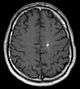

Diagnosis is generally made by magnetic resonance imaging (MRI), particularly using a specific imaging technique known as a gradient-echo sequence MRI, which can unmask small or punctate lesions that may otherwise remain undetected. These lesions are also more conspicuous on FLAIR imaging compared to standard T2 weighing. FLAIR imaging is different from gradient sequences. Rather, it is similar to T2 weighing but suppresses free-flowing fluid signal. Sometimes quiescent CCMs can be revealed as incidental findings during MRI exams ordered for other reasons. Many cavernous hemangiomas are detected "accidentally" during MRIs searching for other pathologies. These "incidentalomas" are generally asymptomatic. In the case of hemorrhage, however, a CT scan is more efficient at showing new blood than an MRI, and when brain hemorrhage is suspected, a CT scan may be ordered first, followed by an MRI to confirm the type of lesion that has bled.